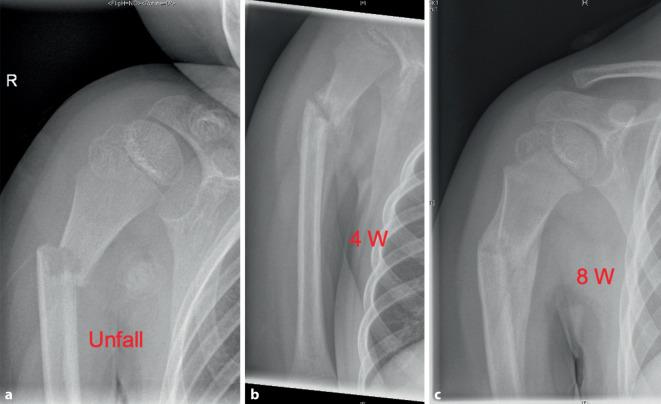

The measurement of axial deviation and tilt is not interobserver and intraobserver reliable [3]. The age limit for when complete correction is possible was set at an age of 10 years, as the correction potential changes around this age. For diagnostic purposes, well-centered X‑ray images in 2 planes (true AP and Y‑images without thoracic parts) is defined as the standard. At the age of less than 10 years, any malposition can be treated conservatively with Gilchrist bandaging for 2-3 weeks. Surgery can only be indicated in individual cases, e.g., in the event of severe pain or the need for rapid weight bearing. An ad latus displacement of more than half the shaft width should not be tolerated over the age of 10 years. Due to the variance in the measurement results, it is not possible to recommend surgical treatment depending on the extent of the ad axim dislocation. As a guideline, the greater the dislocation and the closer the child is to growth joint closure, the more likely surgical treatment is indicated. The development should be taken into account. The gold standard is retrograde, radial and unilateral ESIN osteosynthesis using two intramedullary nails. Osteosynthesis does not require immobilization. A follow-up X‑ray is planned for unstable fractures without osteosynthesis after 1 week, otherwise optional for documentation of consolidation after 4-6 weeks, e.g., if sports clearance is to be granted and before metal removal (12 weeks).

Recommendations for surgical indications based on the extent of tilt are not reproducible and seem difficult in view of the current literature [3, 9, 12]. A pragmatic approach is recommended. The prognosis of the fracture appears to be so good, taking the algorithm into account, that restitutio ad integrum can be expected in most cases.